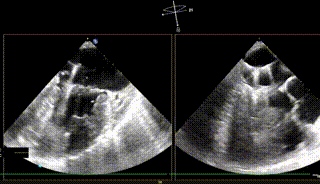

【二尖瓣相关参数】二尖瓣重度反流(继发性:Carpentier II型);A3:21mm P3:13mm,MVOA:5.3cm²,P3脱垂连枷,3区病变,瓣叶质地欠佳。

术前反流

反流基本消失